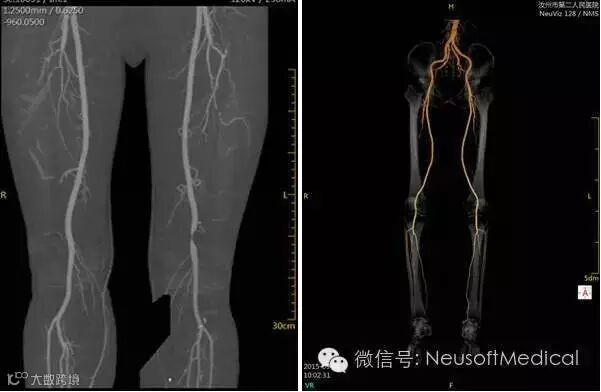

左:双下肢CTA造影,清晰显示左侧股动脉远端重度狭窄

右:正常下肢动脉CTA造影